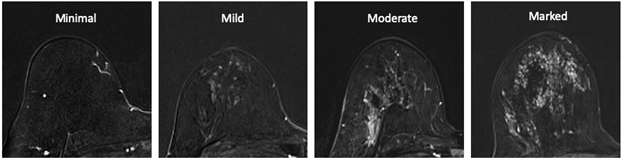

BI-RADS lexicon for the background parenchymal enhancement.

Figure 2: BI-RADS lexicon for the background parenchymal enhancement.